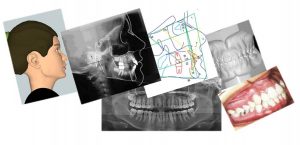

Documentação ortodôntica

Documentação Ortodôntica (6 tipos)

É um conjunto de exames para uma análise completa do paciente, a CERO disponibiliza 6 tipos de Documentações, da básica à mais avançada, favor consultar os tipos abaixo: